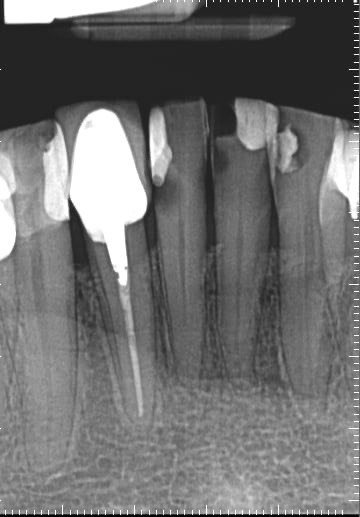

15. What condition can be seen on the buccal surface of the tooth # 4.2?

16. What condition can be seen in distal of tooth # 3.7?

17. What condition can be seen in distal surface of the tooth # 4.7?

18. What condition can be seen in buccal surface of the teeth # 1.1 ans 2.1?

19. What is the condition on the distal surface of the tooth # 3.7?

20. what condition can be seen in buccal surface of 4.4 and 4.5?